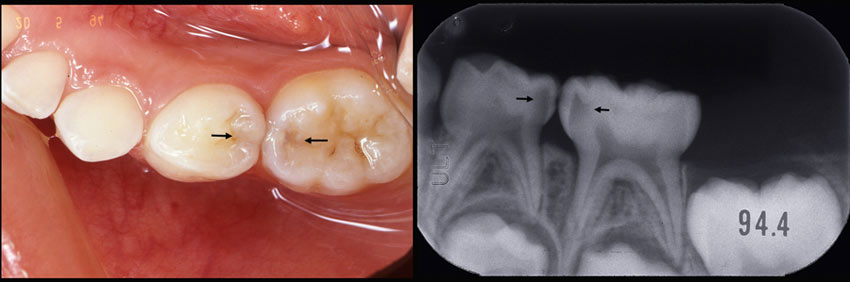

一見何でもなさそうですがレントゲンでは大きな虫歯が確認できます。鮮明なレントゲンであれば素人の患者さんにも虫歯であることがわかります。